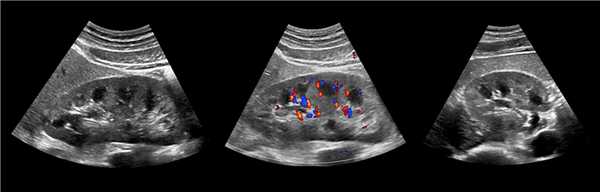

Рисунок. У новорожденного на УЗИ почек определяется гидронефроз (1) и расширенный мочеточник (2) справа. В мочевом пузыре двустороннее уретероцеле (3). При исследовании левой почки структурных изменений не выявлено.

Рисунок. На УЗИ определяется удвоенная чашечно-лоханочная система, расширена лоханка верхнего сегмента (1) и мочеточник на всем протяжение (2, 3), в мочевом пузыре уретроцеле (4). Полное или неполное удвоение чашечно-лоханочной системы возможно увидеть с помощью КТ-урографии.

Рисунок. Дистальный отдел мочеточника расширен, в мочевом пузыре анэхогенное образование с тонким и ровным контуром — уретероцеле.

Рисунок. Двустороннее уретероцеле на УЗИ: в режиме ЦДК из верхушек уретероцеле определяется выброс мочи.

Рисунок. На УЗИ в уретероцеле определяется гиперэхогенная структура с акустической тенью — камень. Уретероцеле может являться одним из факторов, способствующих камнеообразованию.